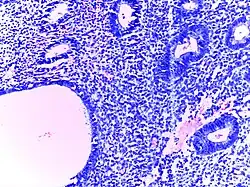

Adenocarcinoma colon | Micrograph of carcinoma colon showing malignant glands.Nuclei are small and vesicular, located at the bottom of the cell. The cells show increased nucleocytoplasmic ratio. | Category: Histopathology of colorectal adenocarcinoma | Colorectal carcinoma |

![]() |